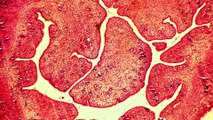

L’endométriose touche 1 femme sur 10 en âge de procréer. Dans son livre « Revivre » publié aux éditions Robert Laffont, Lorie raconte son combat contre cette maladie.